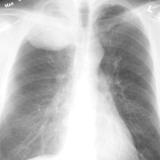

Nodules & Masses

Album: Nodules & Masses

Date: 01/25/2006

Size: 37 items

Views: 59773